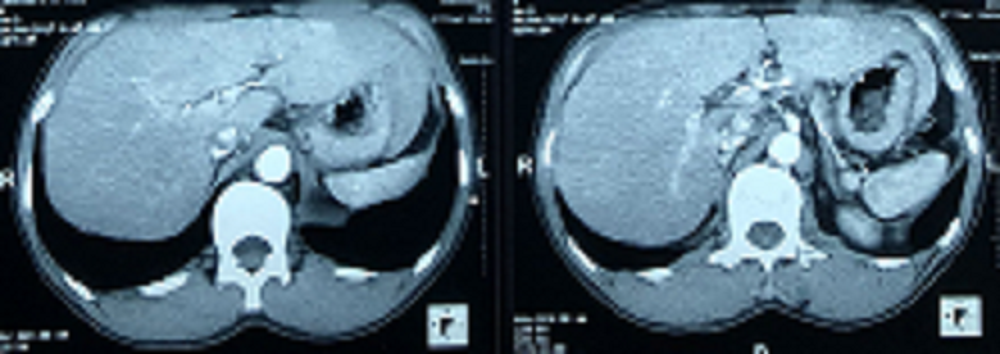

- Chụp cộng hưởng từ sọ não: không có tổn thương bất thường.

Hình 2: Hình ảnh chụp cộng hưởng từ sọ não có tiêm thuốc đối quang từ